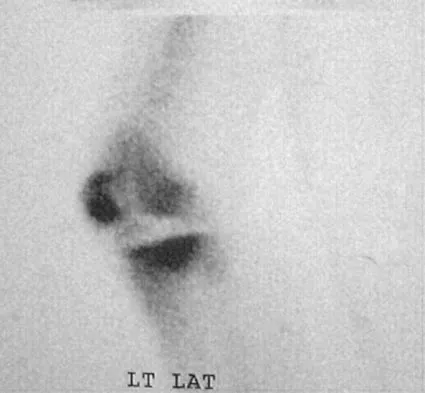

A 48-year-old woman has knee pain that is worse with weight bearing. She reports no night pain or pain at rest. History reveals that she underwent total knee arthroplasty with cementless components 2 years ago. Examination reveals tenderness along the medial joint line. Figures 12a through 12c show radiographs and a bone scan. What is the most likely cause of the patient's pain?